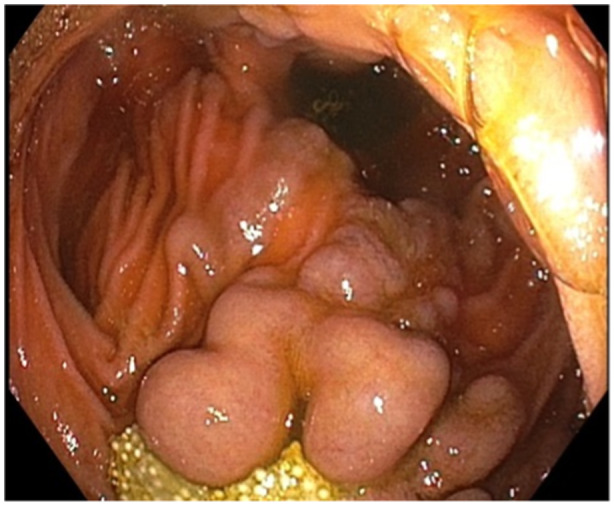

Ectopic varices are defined as portosystemic venous collaterals occurring in the gastrointestinal tract outside of the cardio-esophageal region. Duodenal varices are not routinely encountered by pediatric gastroenterologists. At the time of this case report, there are no consensus guidelines on the management of bleeding duodenal varices in pediatric patients. This is a case of a 14-year-old young woman with a history of multi-visceral transplantation due to short gut syndrome. The patient had developed duodenal varices near her transplant anastomosis, which were incidentally biopsied on endoscopy causing resultant bleeding that required endoscopic hemostasis. This case highlights the need for recognition of duodenal varices as a potential etiology of gastrointestinal bleeding in children and describes band ligation as an effective hemostatic modality.

Abstract Image